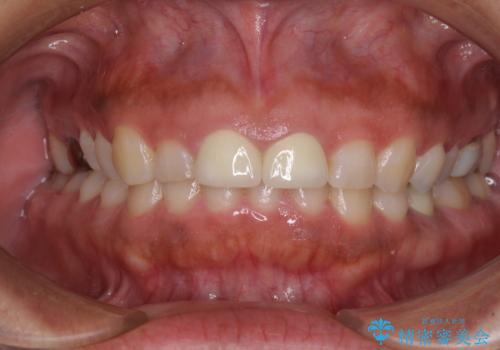

治療を提供する側からすると、歯が短すぎるように思えますが、患者様としては長年気になっていた形態が改善され、大変満足していただきました。